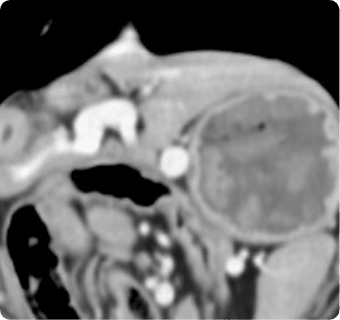

진단하는 핵심센터입니다. 고화질 CT와 초음파, 디지털 엑스레이, 투시촬영기기(C-arm)을 사용해

빠른 촬영속도를 통해 마취시간을 최소화 하며, 선명한 3차원 영상을 구현합니다.

종양, 전이평가, 선천적 혈관 기형 등 여러 질환의 조기 발견 및 환자상태를 평가합니다.

폐 실질 평가, 폐 염전, 폐 종양, 종격동 종양, 심장종양, 폐 전이 평가, 기관, 기관지, 식도의 평가, 복막심낭횡격막탈장, 동맥관개존증